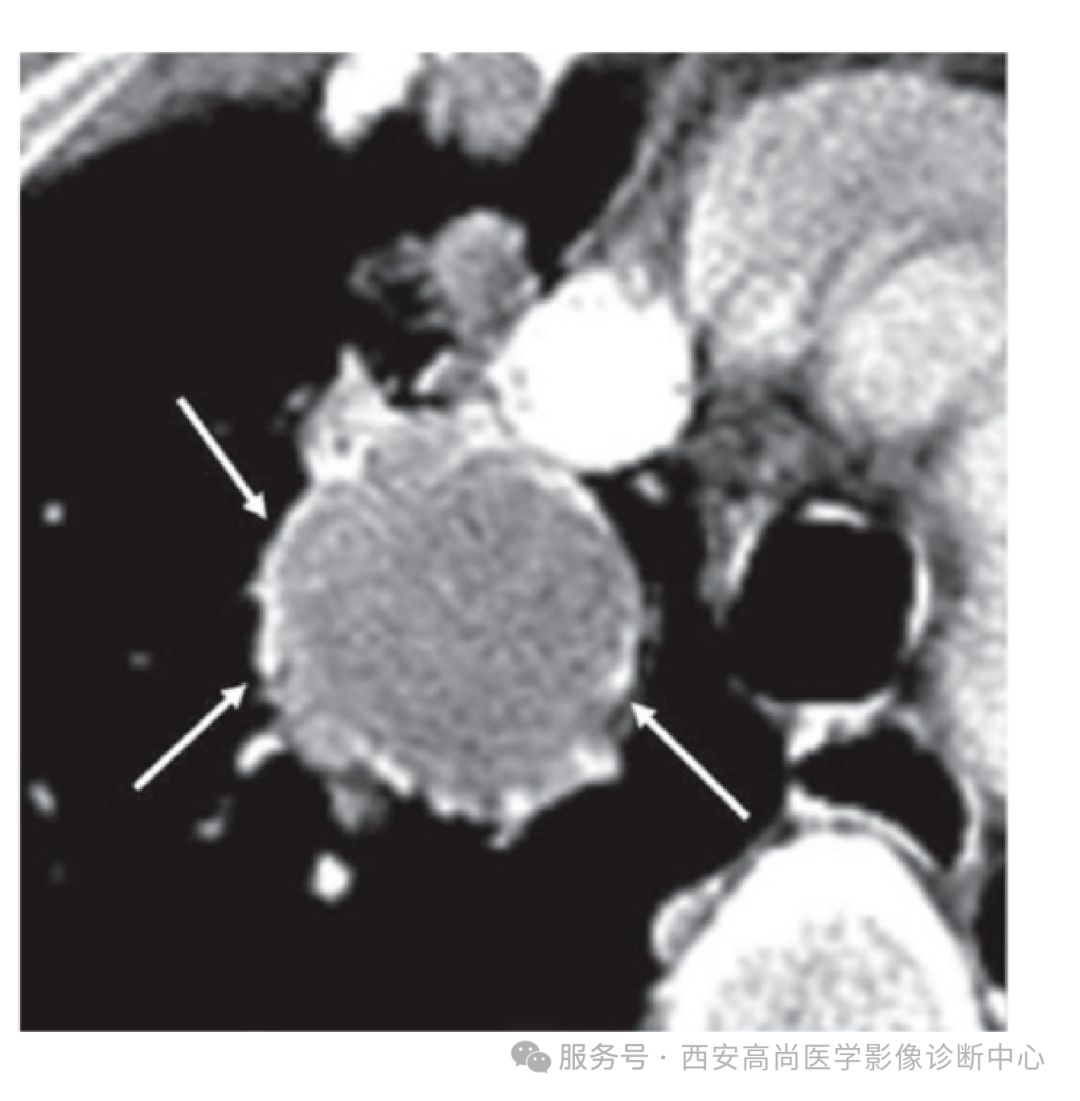

检查所见:右肺中叶见不均匀团块状软组织病变,大小约 8.0 cm×6.3 cm×7.0 cm,右肺中叶支气管完全闭塞,肿块呈高低混杂密度,边界较为光整,其内见点状钙化灶,呈不均匀放射性摄取异常增高,SUV 最大值介于 2.6-6.0。

PSP 复杂的病理结构决定了其影像表现的多样性:

贴边血管征: 是 PSP 增强扫描的特征影像表现之一是病灶周围受推挤的粗大血管影或断面血管影,早期强化明显且先于病灶本身强化;

晕征:表现为病灶周围的磨玻璃样改变,可能是病变周围组织炎性渗出或瘤体伴发出血;

空气新月征:病理基础尚不明确,瘤体可能存在破裂,局部与气管相通形成;

假包膜征: 病灶周围邻近肺组织受压,形成类似包膜结构包绕病灶,增强 CT 扫描时病灶边缘呈线状高密度影;

尾征: 表现为肿瘤边缘的尾状突起,且多位于病灶靠近肺门一端,其发生与 PSP 对肺门血管有生长趋向性有关;